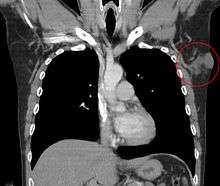

| Histopathological image of dermatofibrosarcoma protuberans. Local recurrence long after the first excision. H&E stain | |